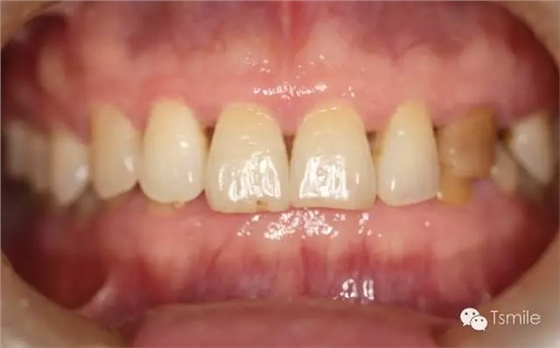

圖2: 前牙功能范圍受限導(dǎo)致的前牙重度磨耗 磨損是指在非下頜功能運(yùn)動(dòng)和副功能運(yùn)動(dòng)中,除牙齒以外的其它物體對(duì)牙齒表面機(jī)械摩擦而導(dǎo)致的牙齒表面硬組織缺損。 磨損患者一般有某種特殊的生活習(xí)慣或工作習(xí)慣,如不正確的刷牙方式、長時(shí)間叼煙斗、咬指甲、咬鉛筆等生活和工作習(xí)慣。長時(shí)間的不良習(xí)慣,這些煙斗、鉛筆、指甲等異物會(huì)對(duì)牙齒表面過度機(jī)械摩擦,導(dǎo)致牙齒表面硬組織缺損。